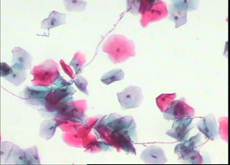

2.1 液基细胞学检查的一般情况 在细胞学检查2200例中,除3例标本不满意外(即标本中上皮细胞少于10%,血液黏液较多),以2197例受检标本纳入分析,标本满意率为99.86%。正常范围(如图1)及良性反应性细胞改变1939例(88.25%),其中提示霉菌感染(如图2)176例,滴虫感染(如图3)27例,细菌性感染(如图4)18例,HPV感染(如图6)6例,有34例ASCUS以上阳性细胞学诊断。

2.2 液基细胞学阳性结果与阴道镜下活检结果比较细胞学检出异常者34例,阳性检出率为1.54% ,其中不典型鳞状上皮细胞(ASCUS如图5)18例(0.81%),低度鳞状上皮内病变(LSIL如图6)9例(0.41%),高度鳞状上皮内病变(HSIL如图7、8)7例(0.32%),鳞状上皮癌(SCC)0例,不典型腺细胞(AGUS)0例。与阴道镜下活组织病理诊断符合率分别为LSIL94.4% ,HSIL100% 。细胞学阳性者在阴道镜下活检病理结果比较见表1。

图1:正常细胞 图2:霉菌感染

图3:滴虫感染 图4:细菌性感染

图5: ASCUS 倾向高度病变 图6:LSIL-HPV

图7:HSIL 图8:HSIL